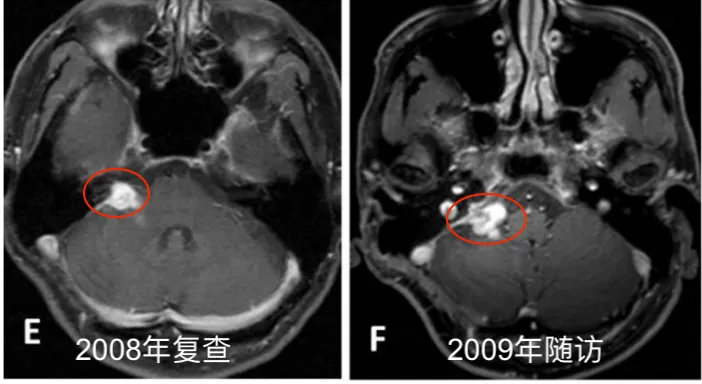

定期随访影像资料(图1 E-J)完整记录2008-2013年肿瘤变化情况。2013年末至2014年初复查显示肿瘤再次生长,2014年4月术前MRI显示肿瘤不均匀强化伴脑干受压。术后两个月随访影像确认次全切除结果。